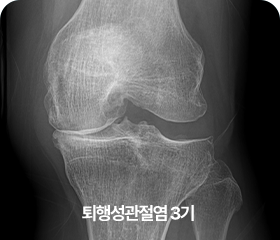

단계별 퇴행성 관절염 증상

3기